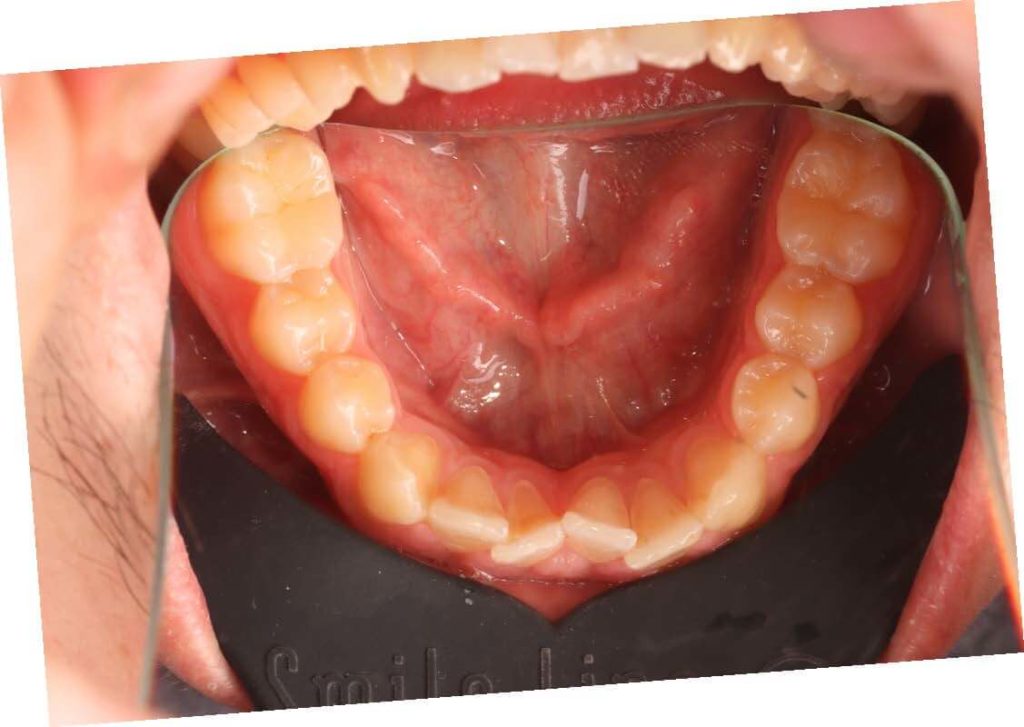

SITUACIÓN INICIAL

CLASE I MORDIDA CRUZADA EN LATERALES

• Clase I con mordida cruzada en los incisivos laterales.

• Apiñamiento moderado en el arco superior e inferior.

• Arco normal con necesidad de expansión.